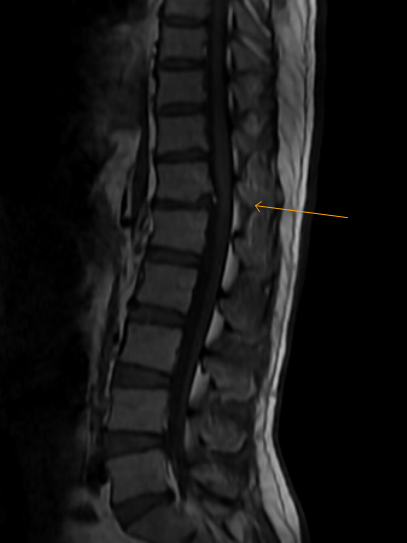

Introduction to lumbar vertebrae anatomy: Vertebra gövdesinin anteriorunun büyük oranda süperiorunda nadiren de inferiorunda yer alan defekte verilen isimdir. Limbus vertebra is a developmental variation that appears radiographically as a small osseous density adjacent to the endplate of one or more vertebral end.

Notice that there are 3 vertebrae involved.

Vertebra gövdesinin anteriorunun büyük oranda süperiorunda nadiren de inferiorunda yer alan defekte verilen isimdir. All four patients have myelographic documentation of herniated disc material affecting the spinal 1 department of radiology, hospital for special surgery, new york, new york 10021. Notice that there are 3 vertebrae involved. These bones give the neck structure, support the skull, and protect the spinal cord, among other functions.